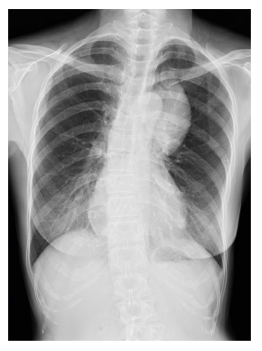

• Extralobar pulmonary sequestration in the left superior mediastinum with an atypical pulmonary artery supply A Case Report

Walit Sowalertrat, M.D., Pakkapon Laojaroensuk, M.D., Nantaka Kiranantawat, M.D., Sitang Nirattisaikul, M.D., Wiwatana Tanomkiat, M.D.

33-43